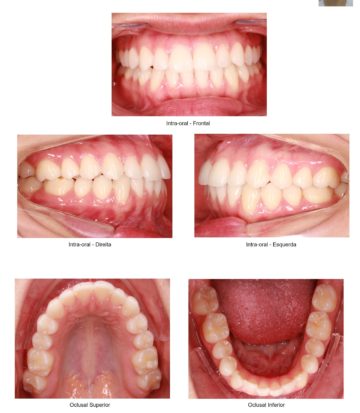

Consiste em um conjunto de exames (radiografias, fotografias intra e extra-bucais, modelos em gesso das arcadas dentárias, análises cefalométricas computadorizadas) cuja finalidade é proporcionar uma visão abrangente do paciente, permitindo que o profissional analise e o auxilie no seu plano de tratamento. Todos esses exames estão contidos em uma pasta e uma caixa específica para colocação dos modelos ortodônticos.

Panorâmica, telerradiografia lateral cefalométrica, 08 fotos intra e extra-orais, modelos de estudo, traçados cefalométricos computadorizados, laudos radiográficos, fichas clinicas, caixa para modelos, pasta de plástico + Série completa.

Panorâmica, telerradiografia lateral cefalométrica, 08 fotos intra e extra-orais, modelos de estudo, traçados cefalométricos computadorizados, laudos radiográficos, fichas clinicas, caixa para modelos, pasta de plástico.

Panorâmica, telerradiografia lateral cefalométrica, 06 fotos intra e extra-orais, modelos de estudo, traçados cefalométricos computadorizados, laudos radiográficos, fichas clinicas, caixa para modelos, pasta de plástico.

Panorâmica, telerradiografia lateral cefalométrica, 08 fotos intra e extra-orais, traçados cefalométricos computadorizados, laudos radiográficos.